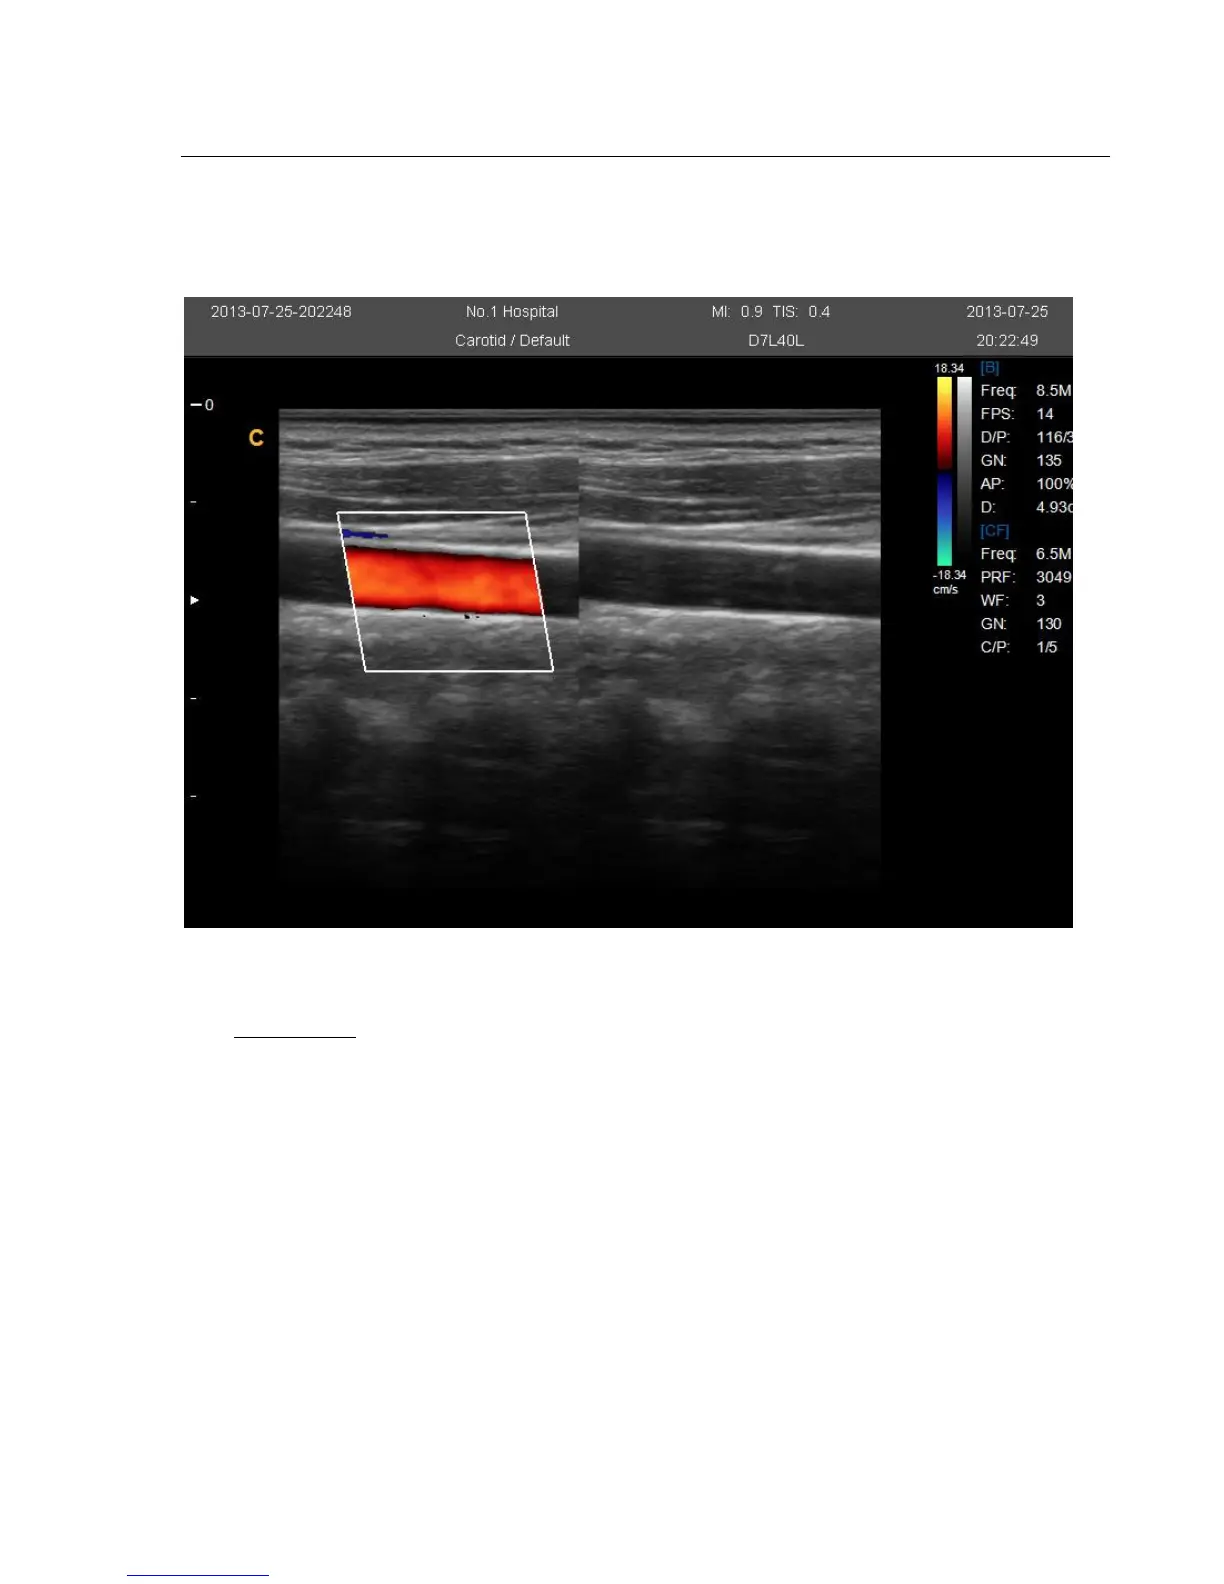

4.3.6. B/BC Mode

In active color mode, turn the [B/BC] item on to display a real B mode image at the left side of the screen and

active Color mode image at the right side of the screen.